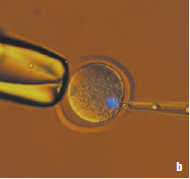

显微操作

显微操作对显微镜系统有极高的要求。以下所示的系统是一个集成式解决方案,包括配备有DFC320摄像机的Leica DMI4000 B、IM1000存档软件以及监测*佳实验条件的附件。

细胞显微操作属于生物医学研究常有的操作技能。机械式徕卡显微操纵器在精确度和质量方面是理想选择。除此之外,我们也提供了电动式或液压式操纵器配Leica DMI倒置显微镜使用。

Leica AM6000* 是显微操作应用的系统解决方案。它能满足*苛刻的显微操作要求。通过与Eppendorf的密切合作,AM6000可以达到*高层次显微操作功能,使Eppendorf显微操作与Leica DMI6000 B倒置显微镜溶为一体,使显微镜操作如此容易。

小鼠卵子染色体移动顺序(紫外线和透射光):

a 移动前; b 吸入移动吸液管;c 移动; d 移动的结果

图像来源:法国Strasbourg (斯特拉斯堡) 的遗传与分子细胞生物学研究所(IGBMC)